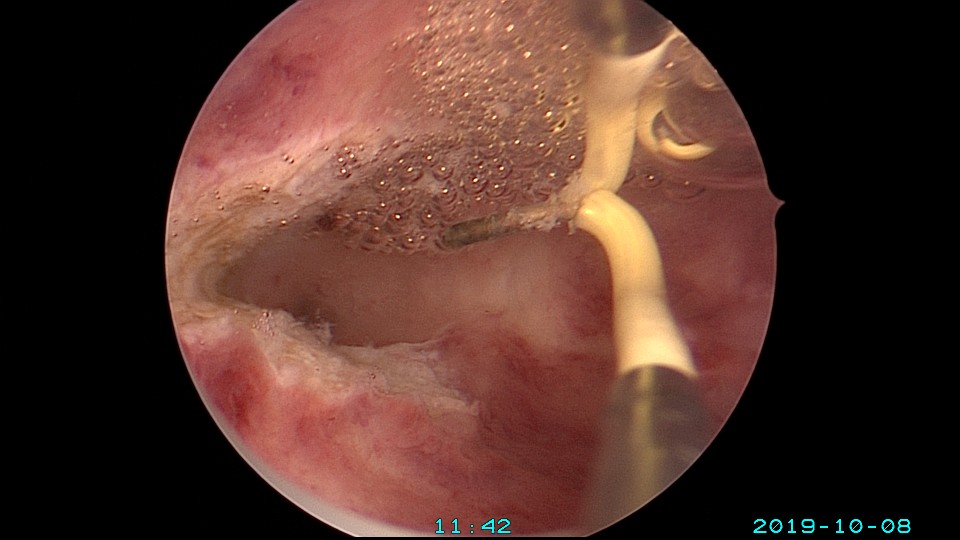

患者27岁,G2P0,人流1次,孕8周胎停清宫1次,绵阳市某医院造影发现宫腔粘连1+月,2019年10月初我院宫腔镜探查,发现宫腔右侧粘连,左侧输卵管开口可见,单极电切分粘,恢复宫腔形态,显露右侧输卵管开口。2019年10月底宫腔镜二探取球囊,宫腔形态正常,双侧输卵管开口可见。2021年10月自然妊娠,稽留流产,我院宫腔镜取胚,2022年再次自然妊娠,足月分泌。现33岁,G4P1。